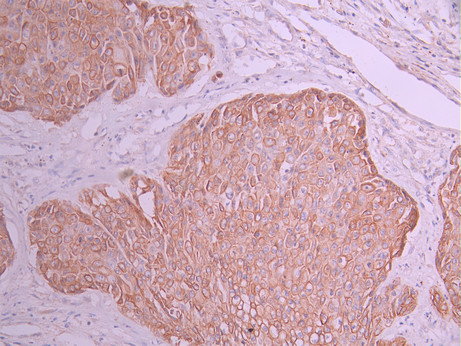

• IHC image of CSB-RA050869A0HU diluted at 1:100 and staining in paraffin-embedded human pancreatic cancer performed on a Leica BondTM system. After dewaxing and hydration, antigen retrieval was mediated by high pressure in a citrate buffer (pH 6.0). Section was blocked with 10% normal goat serum 30min at RT. Then primary antibody (1% BSA) was incubated at 4°C overnight. The primary is detected by a Goat anti-rabbit polymer IgG labeled by HRP and visualized using 0.05% DAB.